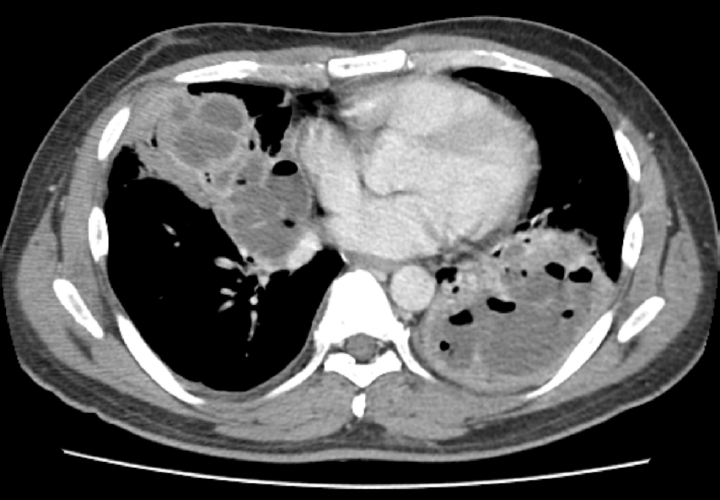

In a small village in Jeollanam-do, Republic of Korea, accounts of a terrible stench had been reported. A 26-year-old man who lived and worked in a foul-smelling area was taken to the emergency room with a headache, dizziness, nausea, and repeated syncope. A subsequent police and Ministry of Environment investigation determined that the cause of the stench was the unauthorized discharge of 9 tons of wastewater containing hydrogen sulfide through a stormwater pipe while the villagers were sleeping. The patient had no previous medical history or experience of symptoms. Leukocytes and cardiac markers were elevated, an electrocardiogram indicated biatrial enlargement, left ventricular hypertrophy, and corrected QT interval prolongation. Myocardial hypertrophy was detected on a chest computed tomography scan, and hypertrophic cardiomyopathy was confirmed on echocardiography. After hospitalization, cardiac marker concentrations declined, symptoms improved, and the patient was discharged after 7 days of hospitalization. There was no recurrence of symptoms after discharge.